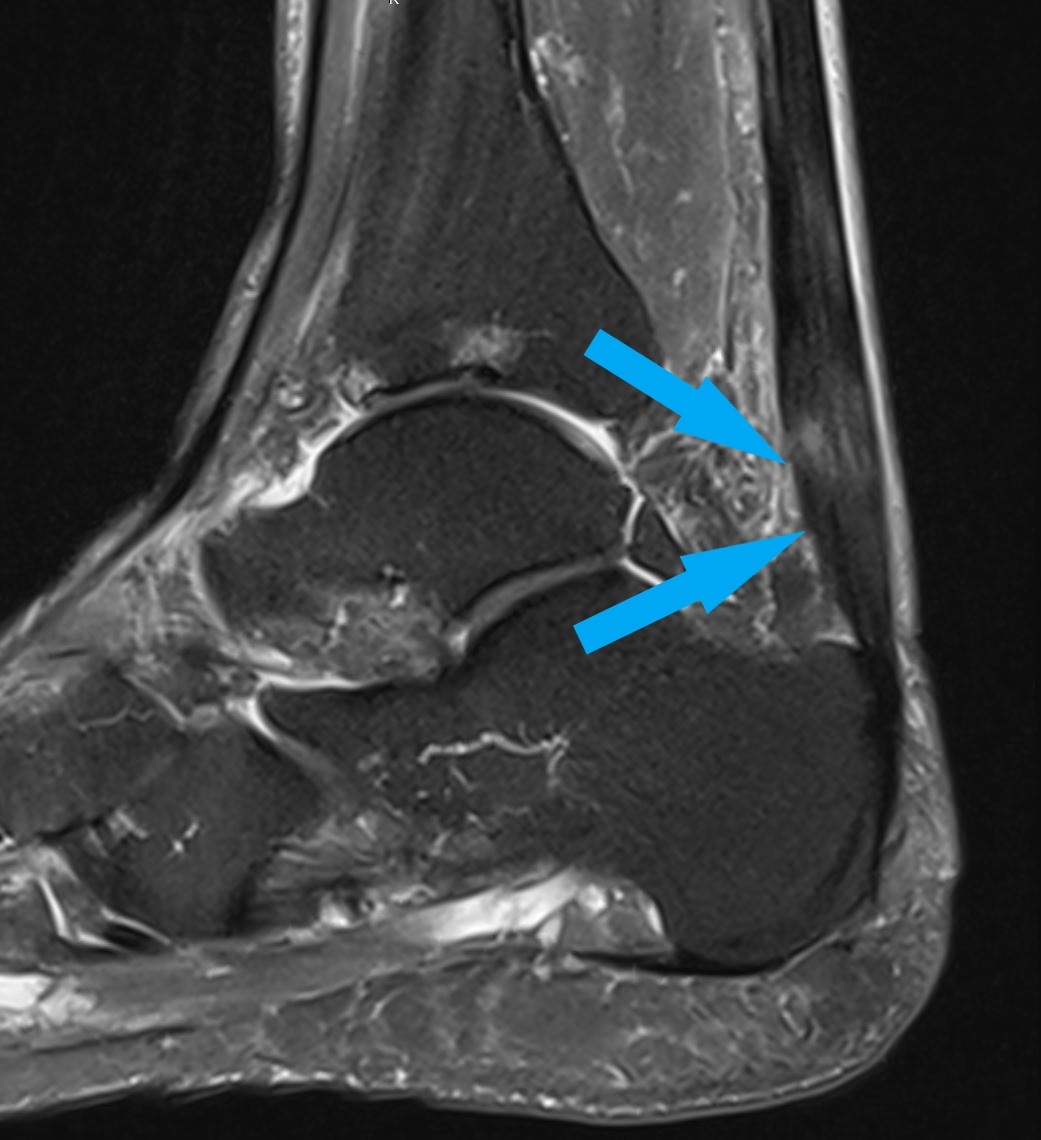

Achillodnyie markiert, mit zentralen Nekrosen

ausgeprägte Achillodnyie markiert, mit zentralen Nekrosen